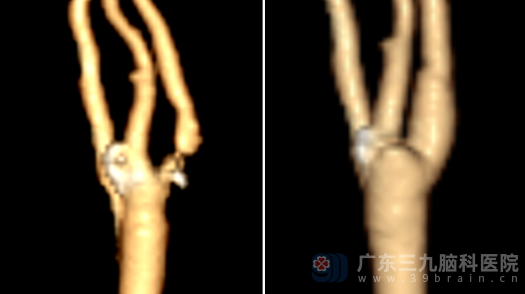

复查颈部CT提示,刘伯的颈动脉血流恢复通畅,狭窄问题彻底解决,这颗“血管炸弹”被成功拆除。

术前CTA 术后CTA